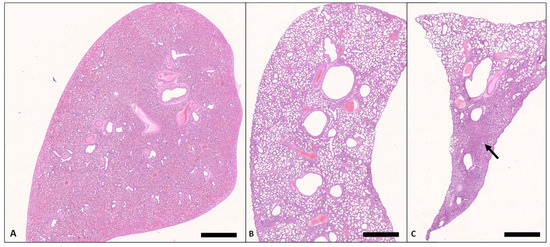

In lung tissue specimens from stillborn pups, sacculi were consistently not unfolded and were judged to be primarily fetal atelectatic (Figure 5A and Figure 6).

Figure 5. Lung, pups, H.E. (A) Dorsal lobe, stillborn, there is diffuse neonatal atelectasia (Bar = 3 mm). (B) Dorsal lobe, death 48 h p.n. Except for marginal areas, the lung tissue is diffusely ventilated (Bar = 1.25 mm). (C) Ventral lobe, death 48 h p.n.; there are abundant areas (arrow) of neonatal atelectasia (Bar = 250 μm).